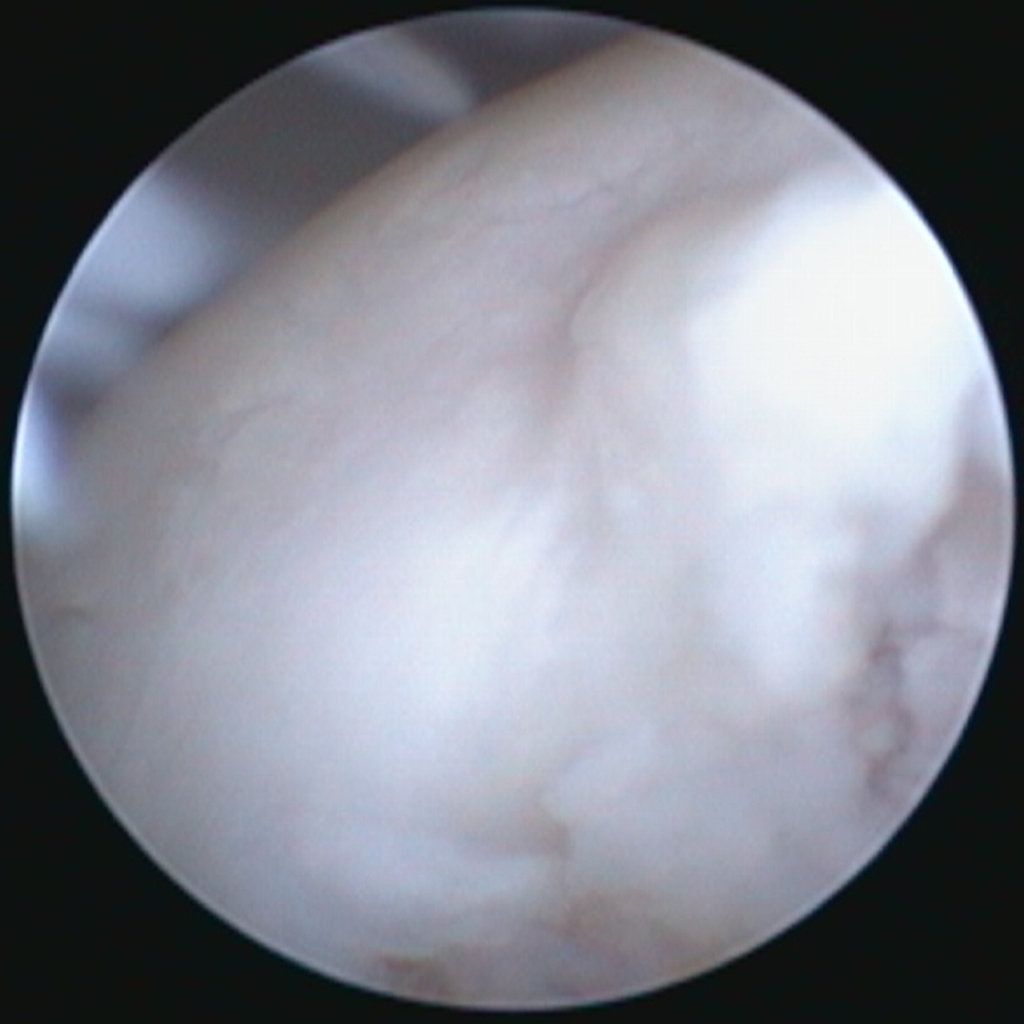

L’IRM n’est pas un examen de dépistage de routine, mais elle rappelle un point fondamental. Le cartilage peut être atteint avant que l’os ne montre des remaniements visibles en radiographie. Dans des contextes particuliers, l’IRM permet d’évaluer les tissus articulaires non osseux et de mieux comprendre certaines douleurs précoces ou atypiques. L’arthroscopie, quant à elle, permet une visualisation directe des surfaces cartilagineuses et peut être indiquée dans des situations ciblées, généralement lorsqu’une décision thérapeutique est envisagée et que l’on souhaite documenter précisément l’état intra-articulaire.

Arthroscopie de la hanche chez un jeune chien de 6 mois présentant une dysplasie sévère avec laxité marquée : aspect de la tête fémorale montrant un cartilage irrégulier avec zones d’érosion et de fibrillation, compatible avec des lésions dégénératives précoces liées à l’instabilité coxo-fémorale.